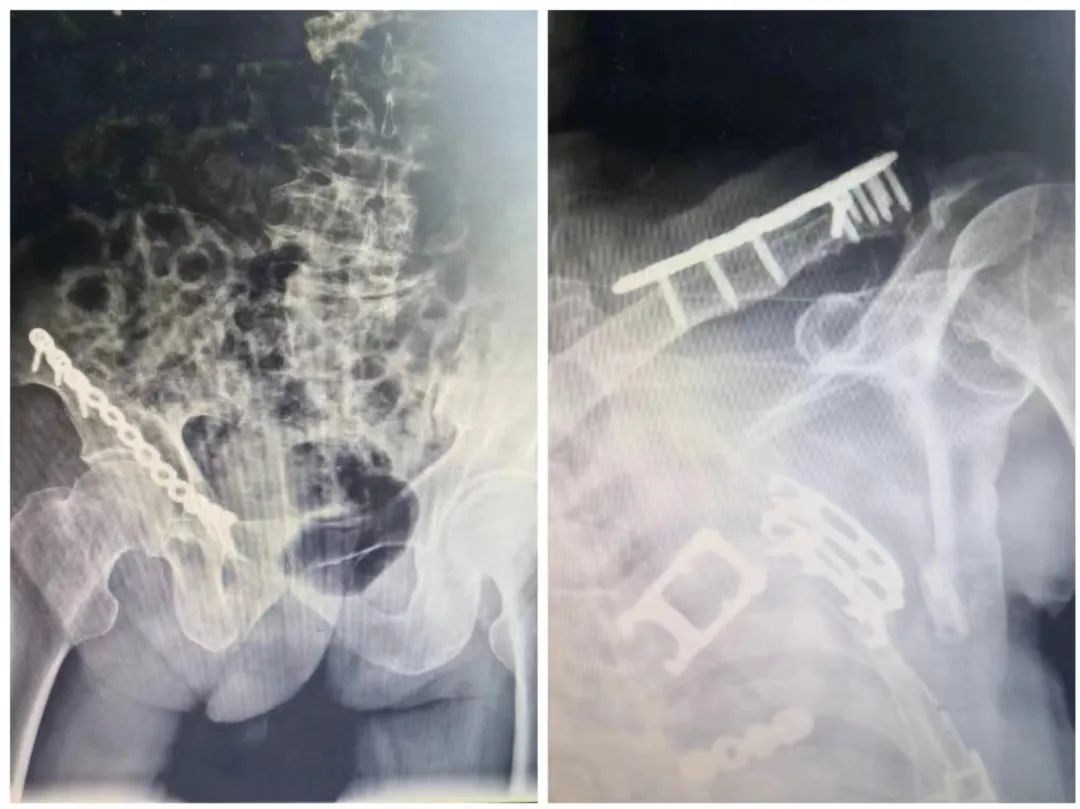

由于是多发伤,患者还伴有骨盆骨折及锁骨骨折,对于护理及后期康复功能上造成很大影响。骨科专家刘春生及吴林生主任团队积极会诊确定手术方式,行骨盆骨折联合微创切口切开复位内固定,左锁骨远端骨折切开复位内固定术,术后恢复良好。经过多学科联合救治不懈努力,患者病情得到了有效控制,生命体征平稳,后续治疗稳步推进。经过一个多月的治疗休养,目前患者康复状况恢复良好。